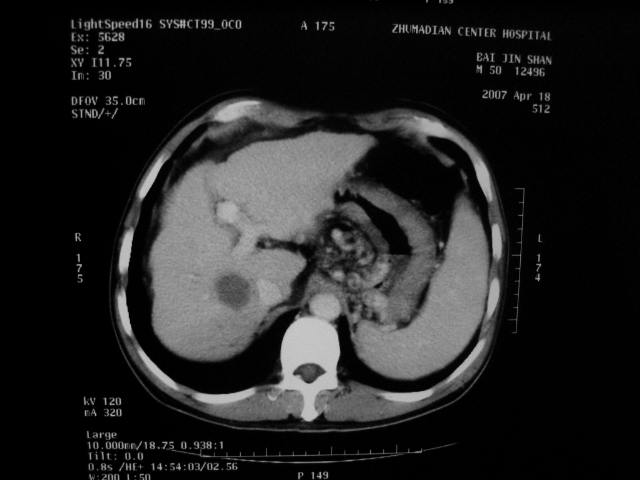

标题: CT7751:病人,50岁,肝硬化多年,行CT三期扫描 [打印本页]

标题: CT7751:病人,50岁,肝硬化多年,行CT三期扫描

1、肝右叶低密度灶考虑肝癌

2、肝硬化

肝硬化、脾大,静脉曲张,肝右叶低密度灶,增强无明显强化,还是考虑肝癌可能性大,建议结合afp检查。

考虑肝硬化,脾大,静脉曲张,肝右叶低密度灶,右肝癌可能性大。

肝硬化一定会有肝癌吗,没有ct值吗,就是一个囊肿